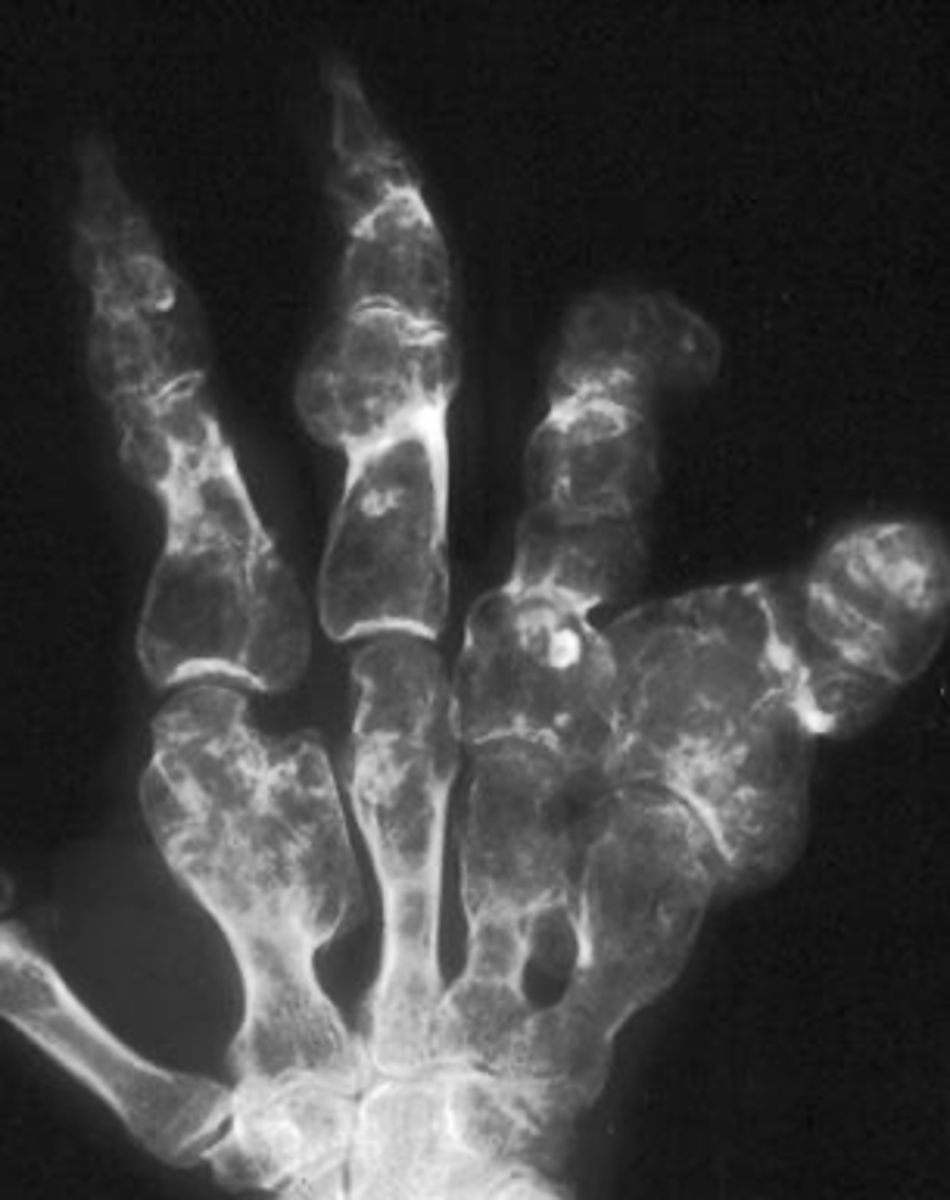

Multiple enchondromas

ID benign tumor